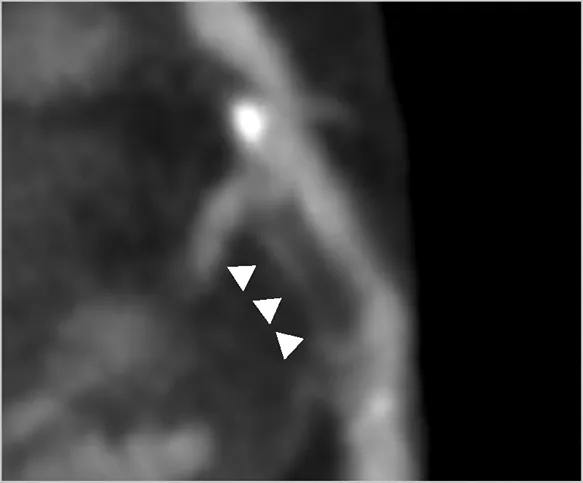

An important CCTA feature relevant for application in clinical trials is the ability to analyse and to quantify specific elements of coronary plaque. Through the use of Hounsfield Unit assessments, CT imaging can detect plaques at various stages of atherosclerosis including calcified plaque, fibrous and fibrofatty plaque, and earlier and more metabolically active lipid-rich plaques. Additional data can include markers such as pericoronary and epicardial fat. Several high-risk plaque (HRP) features are associated with higher rates of clinical events (23), such as low-attenuation plaque, spotty calcification, positive remodelling, and the so-called “napkin ring sign”. This is particularly valuable if the imaging endpoint is used as an enrichment biomarker for MACE-based studies, or as a pharmacodynamic response biomarker to assess the effect of therapy. Volumetric quantitation and differentiation of plaque subtypes are available with intra-coronary imaging modalities of intravascular ultrasound and optical coherence tomography, but the invasive nature of needing to cannulate and image from within a coronary artery limits wide applicability. These interventional techniques are also limited to larger more proximal vessels and can be difficult to pass through severely stenotic lesions. Fortunately, accuracy of CCTA to analyse plaque morphology compares favourably with these invasive techniques (24–26). However, for purposes of measuring potential benefits of new therapeutic interventions targeting plaque, the most consistent CCTA endpoints involve the change in volume or percentage of non-calcified plaque (Table 1) with the additional advantage of being a continuous quantitative variable. The advantage of non-calcified plaque over total plaque burden is due to the observed increase in coronary calcification with stabilisation or regression of other types of plaque. This can result in an apparent neutral change or even an increase in total plaque volume despite overall plaque stabilisation. Furthermore, non-calcified plaque is also associated with higher risk plaques, and is plaque that is more likely to be modified by medical therapy.

Outcome measures selected for each study were consistent across the trials, with standard features of coronary plaque being reported such as total plaque volume, non-calcified volume and high-risk features. CCTA was demonstrated to be able to detect significant interval changes within non-calcified plaque in 12 of the 15 trials. Further positive findings in these trials included changes in total plaque volume, non-calcified plaque percentage (of total plaque) and calcified plaque volume.

There is a growing body of evidence for low-attenuation plaque volume as a risk factor for MACE, and this was also used as an outcome measure in several trials (47). However, this is usually a very small proportion of plaque volume in those without advanced active disease, so is harder to measure accurately and may be less reproducible. These additional measures are readily acquired through semi-automated software systems and are therefore appealing to researchers given their ease of collection. High risk plaque features were not demonstrated to reliably change in these included trials which again, likely relates to their small number which made powering for changes in this feature difficult.

Selection of primary and secondary outcomes should focus on plaque volume and morphology (Table 4). The value of these outcomes in regards to reduction in risk of MACE has been discussed above and the evidence supporting this is robust. The plaque morphology outcomes which demonstrated the most change in prior trials were changes in non-calcified plaque. Both non-calcified plaque volume (mm3) as well as non-calcified plaque percentage (of total plaque) have been shown to be suitable markers for assessment of an interventions therapeutic benefit for phase 2/3 studies (Table 1). Additional outcomes which were able to demonstrate changes in the included serial CT trials, which have also been associated with clinical outcomes previously, are total plaque volume and calcified plaque volume. Further secondary outcomes should include high-risk plaque features (spotty calcification, positive remodelling in respect to remodelling index, napkin-ring sign); however these have not been shown consistently to have statistically significant change over 12-months in the included trials, likely due to lack of power. Calcified plaque volume or calcified plaque as a percentage of total plaque should also be included. Higher levels of calcified plaque is a marker for the presence of more plaque overall and therefore higher risk of MACE, however this is known to increase with statin use and can represent stabilisation of previously non-calcified lesions. Given calcified plaque volume needs to be interpreted in the context of the therapeutic and the clinical situation, collecting more information on this outcome would be important to further our understanding.